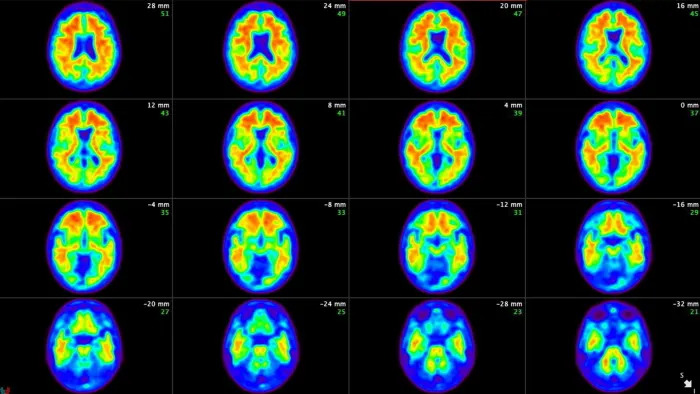

알츠하이머 치매의 원인을 Amyloid 아밀로이드 단백질이 뭉쳐서 생기는 플라크라고 보고 치료약을 개발하고 있다. 이번에 FDA 승인을 받은 LLY Ely Lilly 제약사 Donanemab 신약 원리는 (2번째 그림) 아밀로이드 단백질이 플라크로 발전하는 단계를 차단하는 항체를 유도하는 원리. 그런데, 이상하게 LLY 주가는 오르지 못하고 있다. 왜 그럴까?